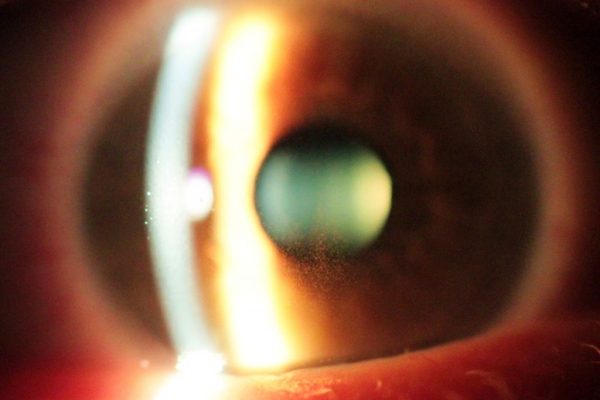

Почему появляется дистрофия сетчатки, до сих пор окончательно не изучено. Офтальмологи рассматривают несколько версий. Пигментная дегенерация сетчатки была названа так из-за изменений, которые происходят в глазном дне, появляются пигментные пятна на глазах. Они образуются вдоль сосудов, расположенных на сетчатке глаза, бывают разных размеров и форм. Постепенно пигментный эпителий сетчатки глаза обесцвечивается, вследствие чего глазное дно просвечивается как паутина из оранжево-красных сосудов.

Со временем болезнь только прогрессирует, а пигментные пятна в глазу все больше распространяются. Густо усеяв сетчатку, они переходят в центральную часть глаза, возникают в радужке. Сосуды становятся очень узкими и практическими невидимыми, а диск нерва бледнеет, позже атрофируясь. Пигментная дегенерация сетчатки обычно проявляет себя на обоих глазах одновременно.

Осматривая пациента, врач сначала изучает качество периферического зрения. Пигментная абиотрофия сетчатки может быть замечена во время осмотра дна глаза. Пятна на радужке, которые напоминают «пауков», станут основной чертой дистрофии. Чтобы поставить точный диагноз используется электрофизиологическое изучение, его считают самым объективным при оценке состояния и функциональных возможностей сетчатки.